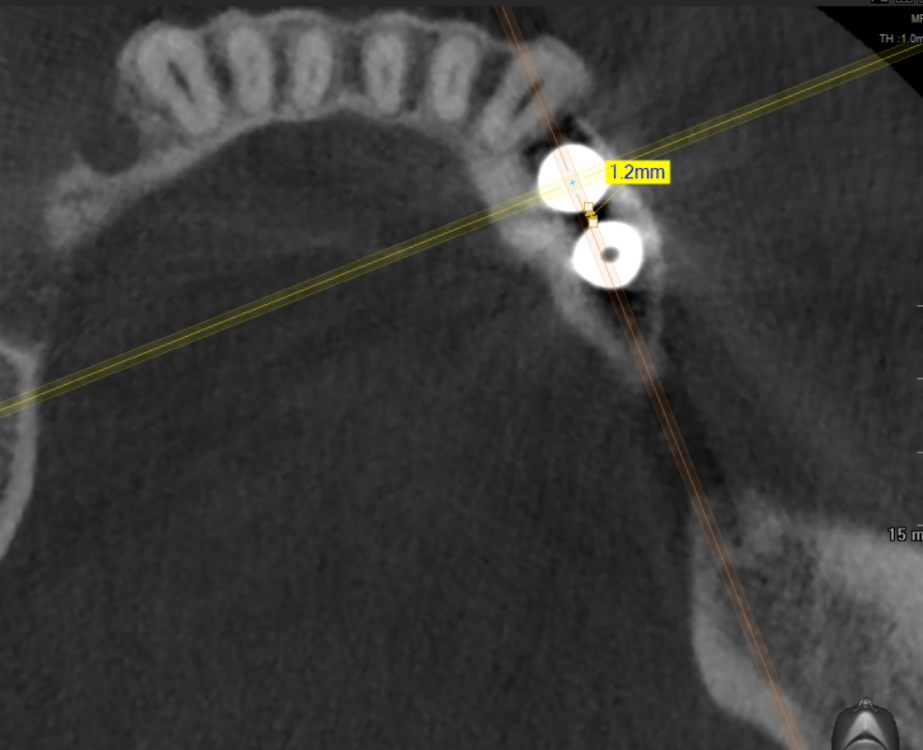

red_butler Опубликовано 22 апреля, 2021 Поделиться Опубликовано 22 апреля, 2021 7 минут назад, m-art-a23 сказал: Нет, не один. Но он лучший. Скажите пожалуйста, что служит причиной боли, по-Вашему? Неужели все импланты нужно убирать только по Кт трудно судить, но есть вопросы по позиционированию имплантов... боль может быть вызвана перегревом кости во время формирования ложа импланта, но в этом случае она появляется примерно с третьего дня. Так же боль может вызывать гиперкомпрессия импланта, и может болеть кость если ее придавили формирователем десны. Я бы обсудил с хирургом удаление среднего импланта слева 1 Ссылка на комментарий

Irouil Опубликовано 22 апреля, 2021 Поделиться Опубликовано 22 апреля, 2021 Я бы рекомендовал удаление среднего импланта слева, независимо от наличия/отсутствия болевых ощущений боль может быть признаком каких-то описанных моим коллегой процессов, а может ничего кроме самой боли не означать (менее вероятно, но и такое бывает). Если удаление упомянутого импланта поможет против болевого синдрома - это win-win если хирург не видит необходимости удаления импланта, я бы рекомендовал сходить на осмотр к ортопеду, который будет в будущем эти импланты протезировать. Возможно у него найдутся весомые аргументы для коллеги 3 Ссылка на комментарий

Irouil Опубликовано 22 апреля, 2021 Поделиться Опубликовано 22 апреля, 2021 (изменено) 1 час назад, m-art-a23 сказал: Благогдарю за совет. Если Вам не трудно, объясните пожалуйста, что не так со средним имплантом. Описанные процессы, если таковые имеют место быть, должны постепенно прийти в норму? Другими словами, сколько еще нужно времени, чтобы окончательно принять решение об удалении импланта (имплантов)? Сегодня третьи сутки после установки. Боль сохраняется. Средний имплант расположен чрезвычайно близко к соседнему, расположенному кпереди от него. С очень большой долей вероятности это может привести к значительной резорбции (убыли) костной ткани между ними, что для любых имплантов очень вредно, а для конкретно Анкилосов - губительно из-за особенностей их протезирования. Если неблаготворные процессы (компрессионный или термический некроз) присутствуют, то импланты просто не интегрируются (не приживутся) - те, что зашиты не выдержат нагрузки при раскрытии, а тот, на котором стоит ФДМ - расшатается через 2-3 недели. Это не призыв проверять его стабильность языком, сейчас его лишний раз лучше не трогать. В норме после имплантации боли держатся 1-2 дня, если все не очень хорошо - держатся 2-3 недели, но даже в таком случае имплант может интегрироваться, поэтому решение об его удалении в таком случае должно, по моему убеждению, быть совместным между врачом и пациентом, и приниматься в индивидуальном порядке Изменено 22 апреля, 2021 пользователем Irouil Ссылка на комментарий